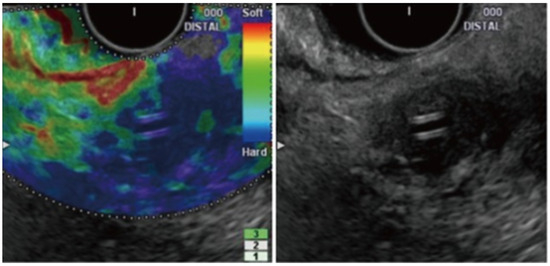

- Strain Elastography (Qualitative Elastography): It estimates the stiffness of the tissue by measuring the degree of strain [29,52]. The results are interpreted with the help of a colored scale, wherein red-green areas indicate softer tissues and blue areas indicate stiffer tissues [29,52]. The main limitations of qualitative elastography are that it lacks reproducibility as the interpretation of the colors is highly operator-dependent, and it provides limited information when comparing results for different patients and lesions [54,55].

- Shear-Wave Elastography (Quantitative Elastography): It measures tissue stiffness by measuring the propagation of the shear waves, which is the emission of focused waves from the probe to the target lesion, also known as acoustic radiation force impulse [29]. Another method of shear-wave elastography is the semi-quantitative analysis, which allows for the measurement of tissue stiffness by calculating the strain ratio (ratio of stiffness of area of interest on the target tissue and smaller region of interest of a reference tissue) and strain histogram technique where an average hue histogram represents the colors and thereby the stiffness of the tissue [56]. It is important to note that only strain elastography is available with EUS for the evaluation and characterization of pancreatic lesions [29].